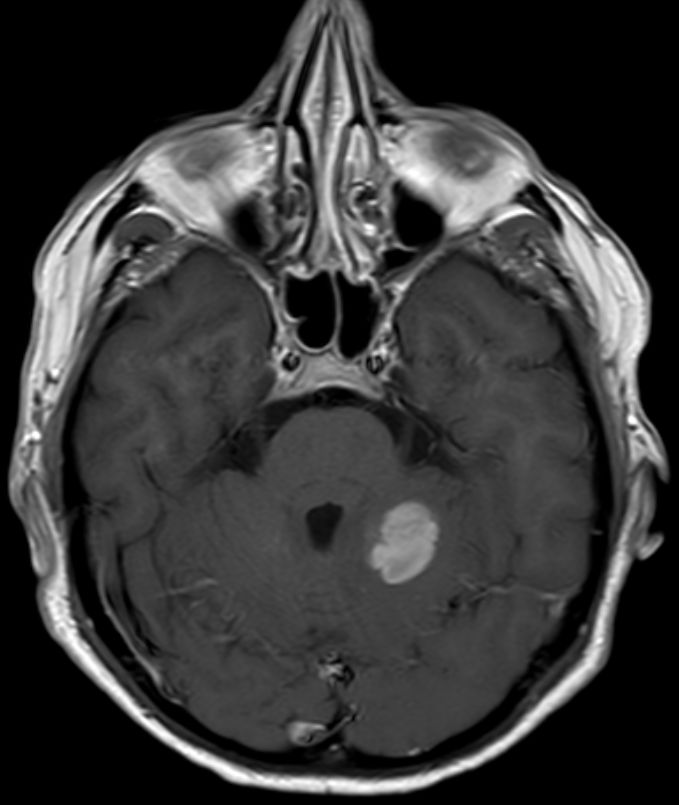

| Hirnmetastasen | OS 6,7 Monate nach Ganzhirnbestrahlung oder oder stereotaktischer Bestrahlung

![]() | |||